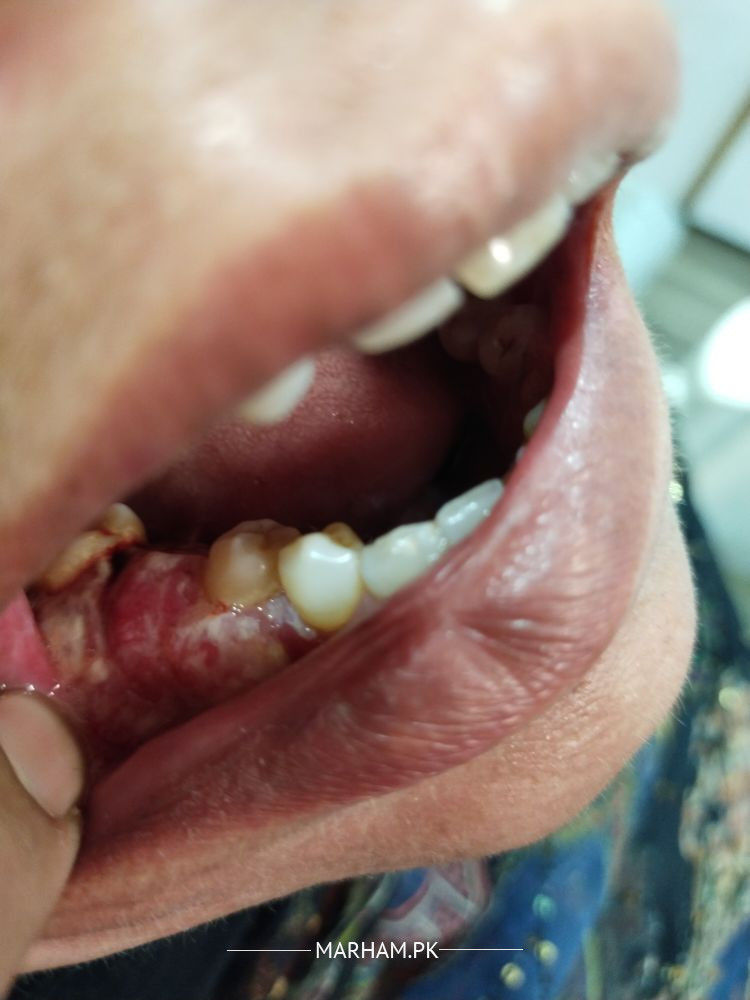

Mari mama k gums ma abnormal skin growth hai shaid swelling hai mouth opening b Kam hai Samaj nae a raha Kya kea jay Kai doctors ko check krwaya unho na medication ki but problem still the same koi advise kr day k kia krna chaiay x ray or gums ki pic attach krdi hai

It is inflammation and hyperplasia og gums,there may be numbers of reasons,plz visit dental surgeon to evaluate and proper treatment, only medines are not enough

it seems suspicious, to be on safe side biopsy must be taken to rule out any pathology

probably nothing but you should get it removed and tested just in case as in a biopsy just to be sure

does she take naswar paan or gotta.biopsy may be needed

It seems to be traumatic gingivitis which is due to supra eruption of upper molar tooth into the lower edentulous space. Root canal treatment of upper molar tooth. Then it will be trimmed to the level occlusal plan. And prosthesis to be given in the lower edentulous space